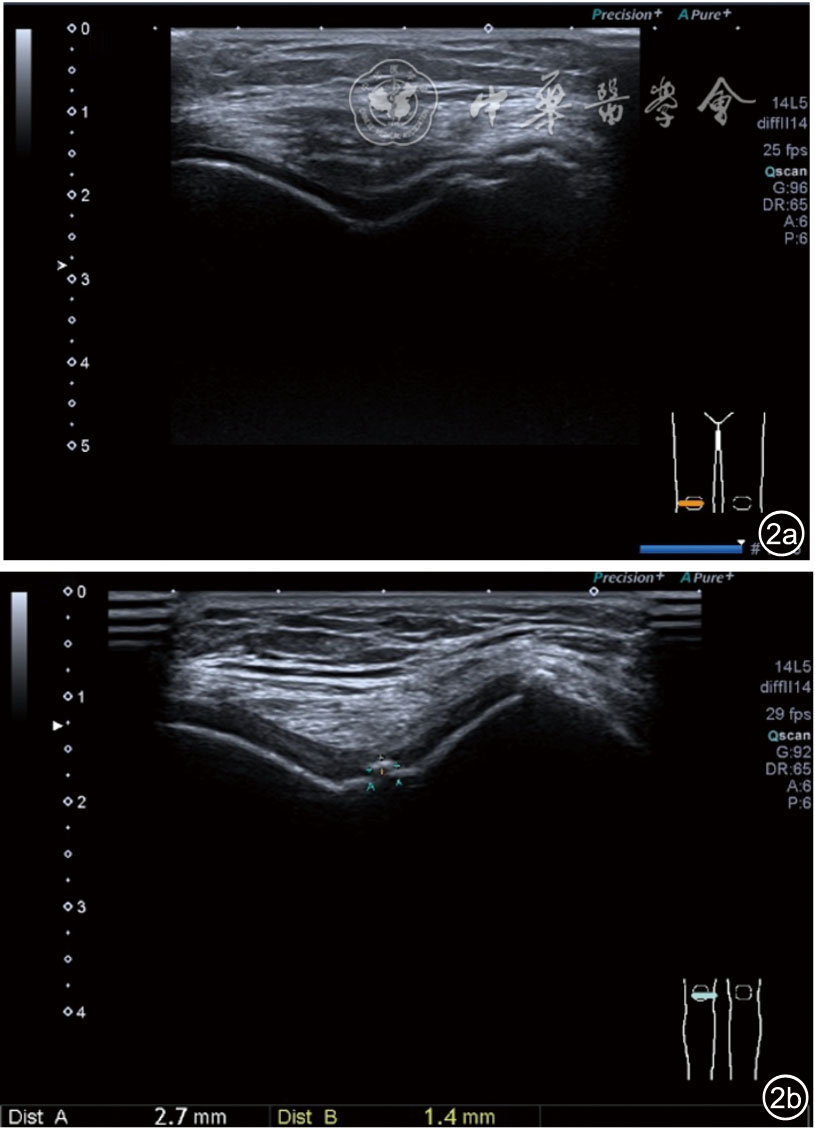

1.关节内表现。(1)骨改变。表现为骨末端或关节周缘出现的骨质局部突起改变,其后方伴或不伴有声影,多见于膝关节内侧缘和外侧缘(图1)。(2)软骨改变。股骨关节面改变可以在长轴及短轴切面显示,嘱患者屈曲膝关节,足平置于检查床,股骨滑车及股骨髁上半部分的关节面即可轻松显示。超声探查可见股骨负重面关节软骨发生不同程度的改变,轻者关节软骨浅侧边界模糊,重者可见关节软骨薄、缺失,软骨下骨缺损改变(图2)。(3)半月板外突。一般内侧半月板突出多见,外侧半月板突出比较少。半月板可见不同程度的外突,同时伴有膝内侧副韧带向外移位(图3)。半月板外周缘性滑脱是指半月板突出超出胫骨平台边缘的距离≥3 mm,其可引起一系列临床症状,早期诊断、早期治疗可以预防骨关节的进一步损伤。(4)交叉韧带损伤。可见前后交叉韧带增粗,回声减低(图4)。(5)髌上囊积液。膝关节是最容易发生积液的关节之一。患者仰卧位,关节积液最常见于膝关节上外侧,因为关节囊向髌股关节上外侧突出。髌上囊积液采用10~18 MHz的高频线阵探头于股四头肌腱纵断面及横断面扫查均可显示,探头频率取决于患者体型。超声可见低回声积液,慢性可伴有丛状滑膜增生(图5)。(6)脂肪垫水肿。脂肪垫在髌骨附着点处回声增强、增厚(图6)。

图2 关节内软骨变薄、缺失,软骨下骨缺损超声图像

3.超声半定量评估。(1)骨赘超声半定量评估:患者仰卧位,膝关节伸直,探头纵切面置于膝关节内侧与外侧,自前向后移动探头以进行全面扫查。测量骨赘的厚度,并进行半定量分析。0级:无骨赘;1级:小骨赘,厚度<2 mm;2级:中等骨赘,厚度2.1~4.0 mm;3级:大骨赘,厚度>4.0 mm。(2)关节软骨超声半定量评估:患者仰卧位,膝关节完全屈曲。探头置于骨上方,检查股骨内侧髁、外侧髁和股骨滑车处关节软骨三个部位,分别进行横切面和纵切面检查,从近侧向远侧做全面扫查。检查时声束要垂直于股骨表面。关节软骨可按病变严重程度分为四级。0级:关节软骨呈均匀的无回声带,其浅侧和深侧边界清晰。1级:关节软骨浅侧边界不清和(或)内部回声增高。2级:①2A级,关节软骨局部变薄,缺损厚度<50%;②2B级,关节软骨局部变薄,缺损厚度>50%,但<100%。3级:关节软骨局部完全消失,伴或不伴有软骨下骨病变。(3)半月板突出分度:半月板外周缘与胫骨平台边缘之间的距离≥3 mm的突出视为病理变化,诊断为半月板周缘滑脱。按照突出程度分为三度:Ⅰ度,半月板外周缘与胫骨平台边缘之间的距离3~5 mm;Ⅱ度,半月板外周缘与胫骨平台边缘之间的距离>5~8 mm;Ⅲ度,半月板外周缘与胫骨平台边缘之间的距离8 mm以上。